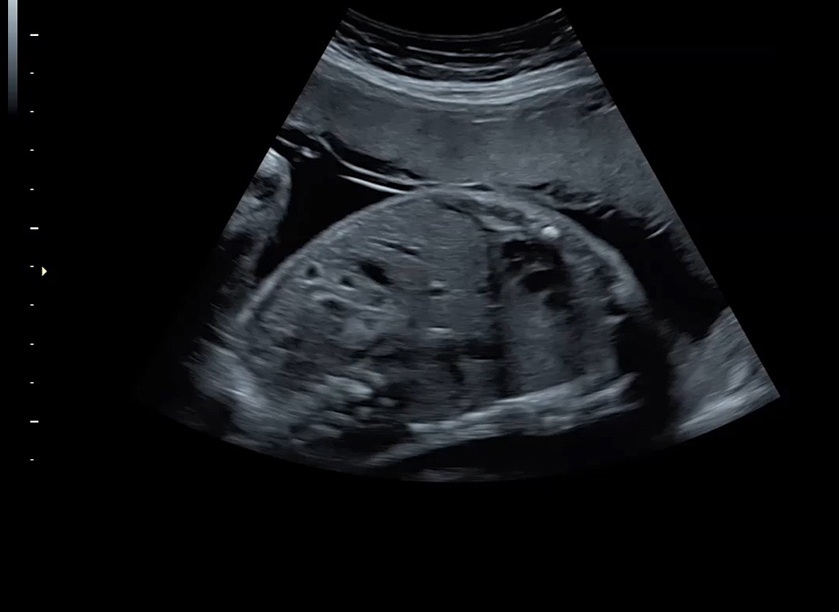

Ультразвуковая платформа Voluson S8 представляет собой оборудование экспертного класса с передовыми возможностями и высоким уровнем автоматизации процессов. Она позволяет проводить сканирование в режимах 2D, 3D и 4D с высоким качеством изображений.

• Высокое качество изображений: Voluson S8 обеспечивает высококачественные изображения, позволяющие детально оценить состояние плода и обнаружить возможные патологии.

• Сложные инструменты для оценки качества плода: Сканер оснащен инновационными инструментами, позволяющими проводить детальную оценку состояния плода, включая его сердечную деятельность, анатомию и кровоток.